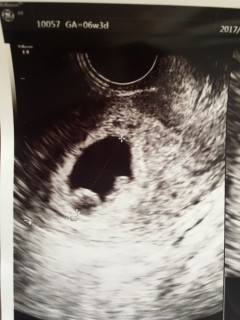

写真:6w3d:れいちゃんさん

はじめての妊娠です。 6週3日ですが、胎嚢は17mm,胎芽は4.4mmでした。心臓らしきものが動いていました。 先々週は全く胎嚢も見えず、不安な1週間でしたが、まずは子宮外妊娠ではなかったとホッとしています。 来週また検診で、母子手帳かなぁーっと先生からの一言でした。

不妊治療等含め、1年半近く待っての妊娠でした。 妊娠判明してから1回目の受診です。排卵日計算で6w2dかと思いきや6w3dだねと言われました。 胎嚢が細長く楕円形で え?まんまるじゃないの?!と思いましたが、ピコピコ点滅している心臓も心音も無事確認できたので良かったです。 赤ちゃんの大きさは3.6mmで小さめかもしれませんが、先生はちょうど6週半ばくらいの大きさだねと言っていました。 胎嚢も胎芽も心拍も確認できたときは、これが私の体の中に起こっている現実が驚きのあまり信じられず、嬉しかったですが変な感じでした。2週間後が楽しみです! 次は夫のためにも、モニターの動画を撮りたいです。

妊娠検査薬で陽性だったため産婦人科受診。6w3dで赤ちゃんの大きさは5ミリだそうです。一応ざっくりの予定日も聞けました。心拍も確認できて、とっても元気ですよ!と。思わず嬉し涙。どうか2週間後の健診でも元気な姿を見れますように。それまでに母子手帳をもらいにいって、2週間後には予定日も確定しそうです!